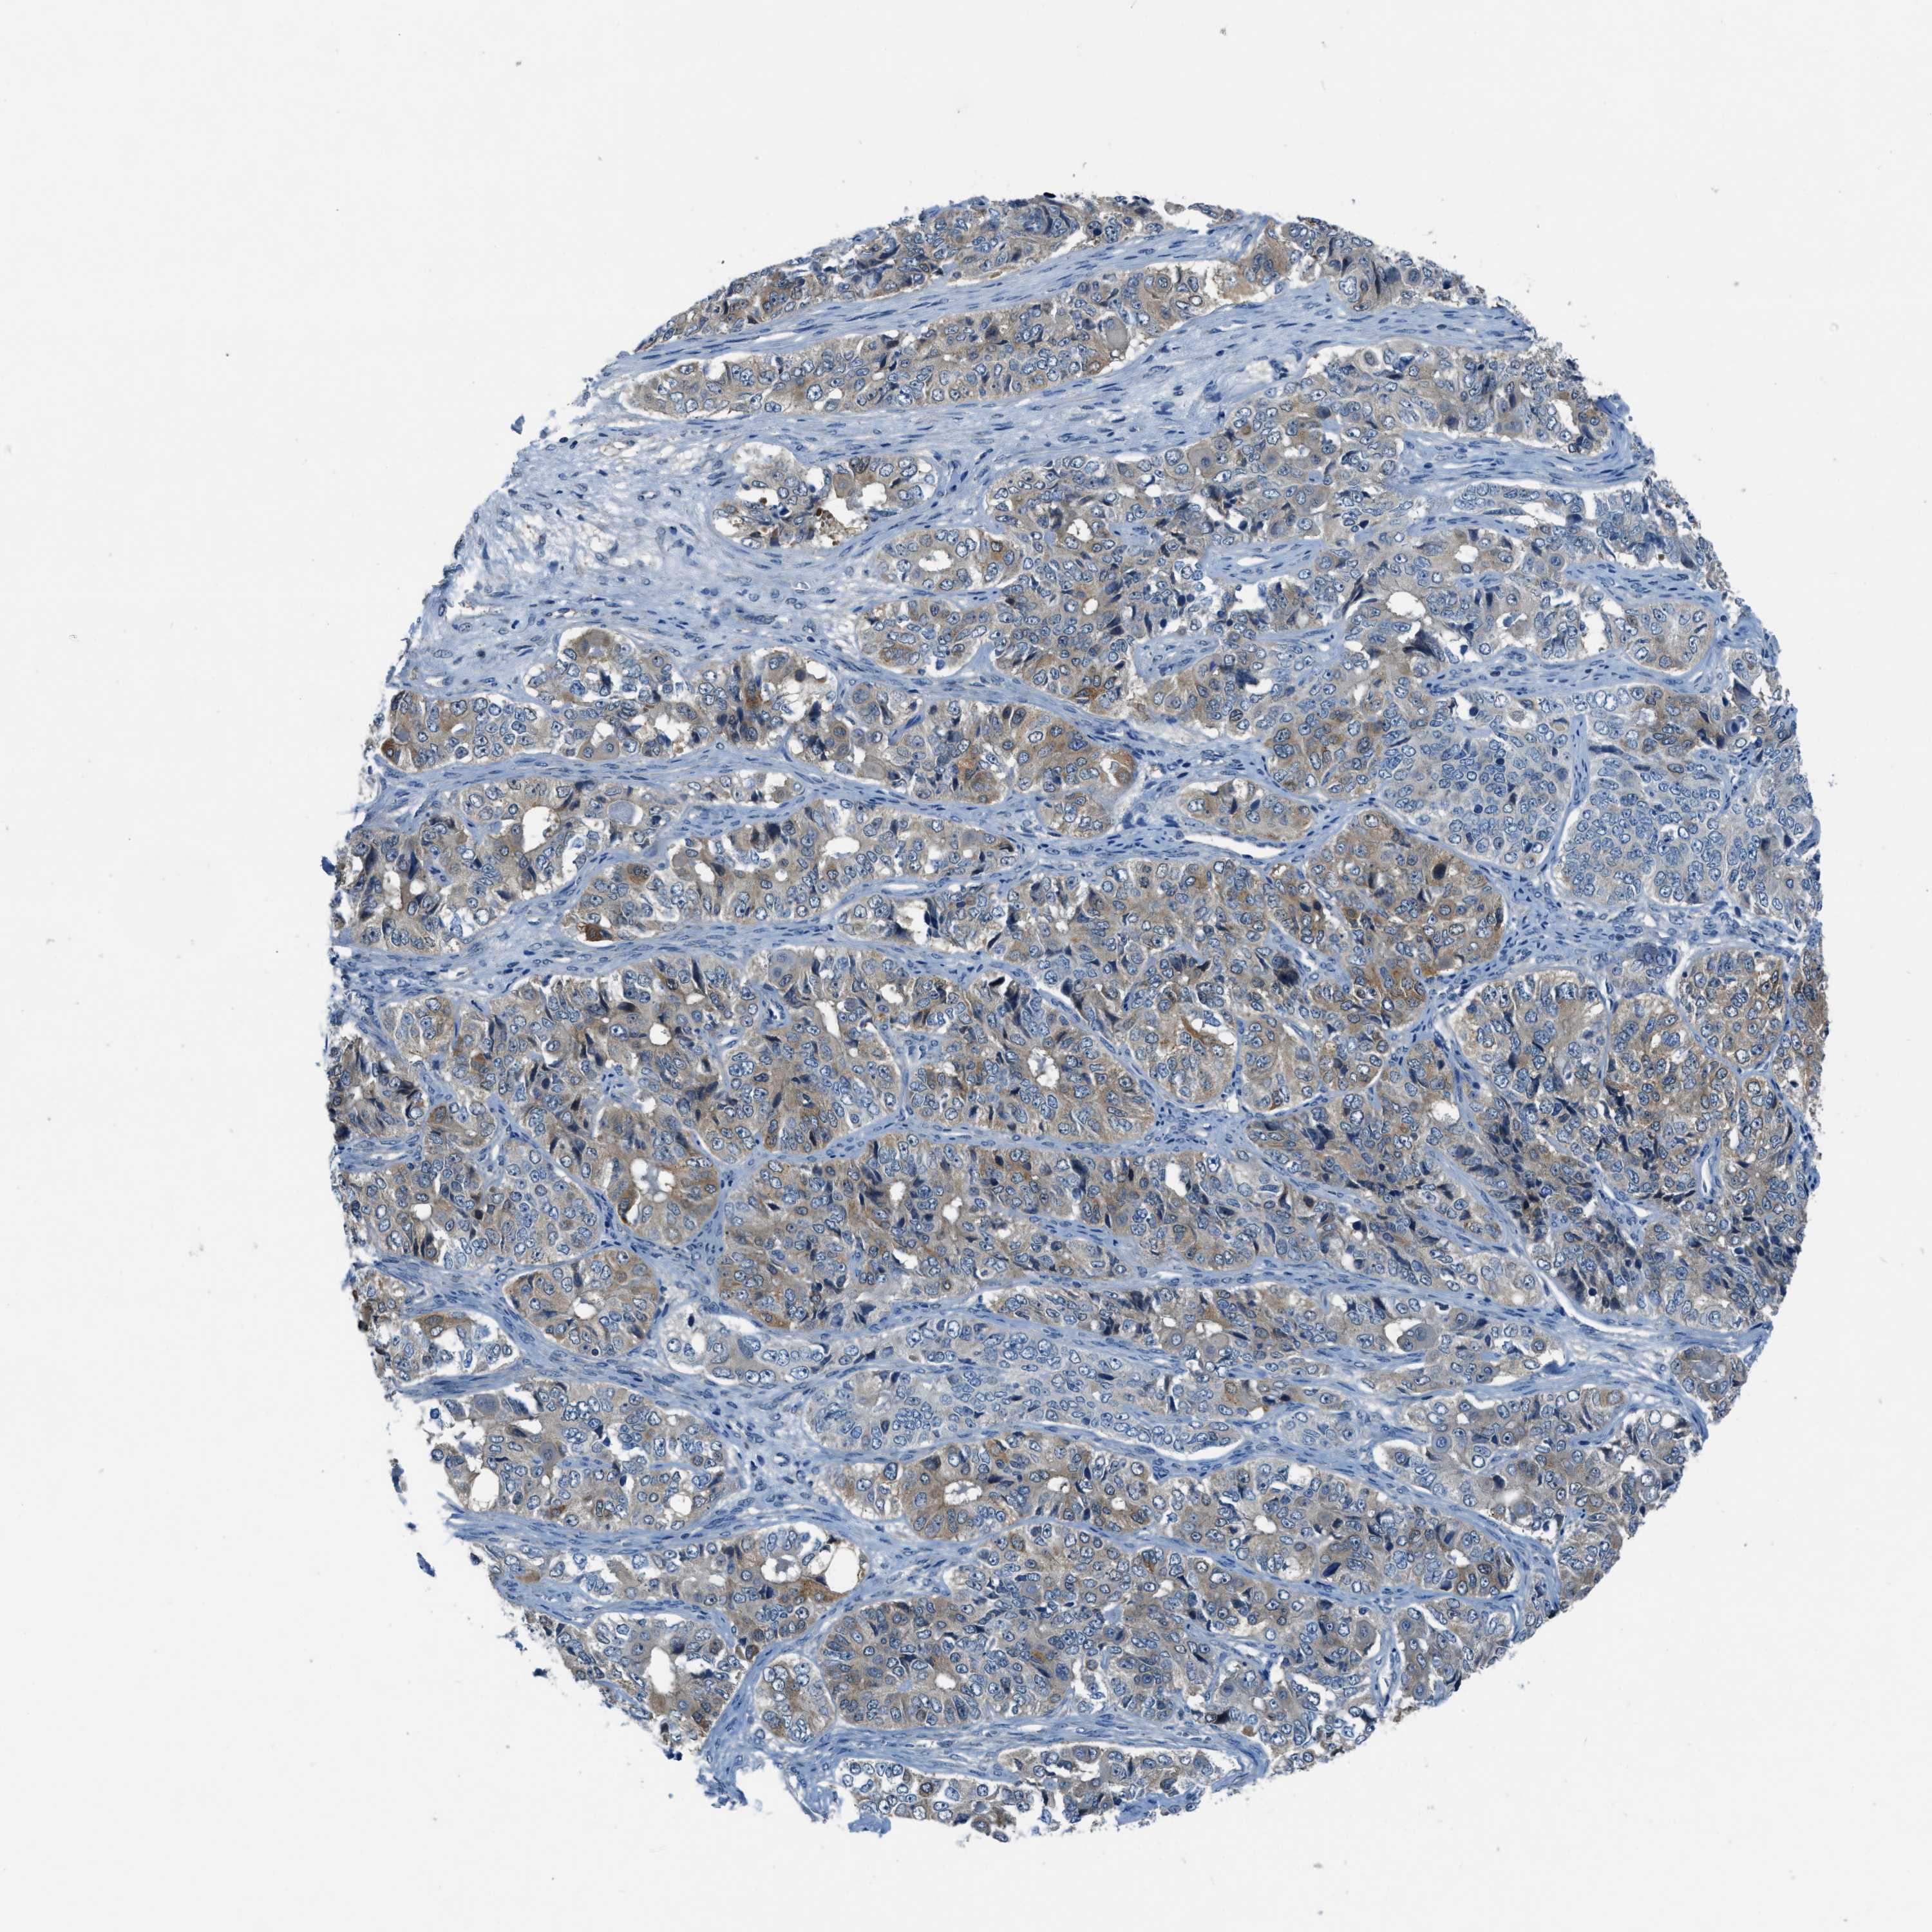

OVARIAN CANCER - Protein expressioni

A mouse-over function shows sample information and annotation data. Click on an image to view it in a full screen mode. Samples can be filtered based on level of antibody staining by selecting one or several of the following categories: high, medium, low and not detected. The assay and annotation is described here.

Note that samples used for immunohistochemistry by the Human Protein Atlas do not correspond to samples in the TCGA dataset.

Antibody stainingi

Antibody staining in the annotated cell types in the current human tissue is reported as not detected, low, medium, or high, based on conventional immunohistochemistry profiling in selected tissues. This score is based on the combination of the staining intensity and fraction of stained cells.

Each image is clickable and will lead to virtual microscopy that enables deeper exploration of all samples and also displays staining intensity scores, fraction scores and subcellular localization as well as patient and tissue information for each sample.

Antibody HPA016649

Antibody HPA018152

Cystadenocarcinoma, serous, NOS

Carcinoma, endometroid

Cystadenocarcinoma, mucinous, NOS

Carcinoma, NOS